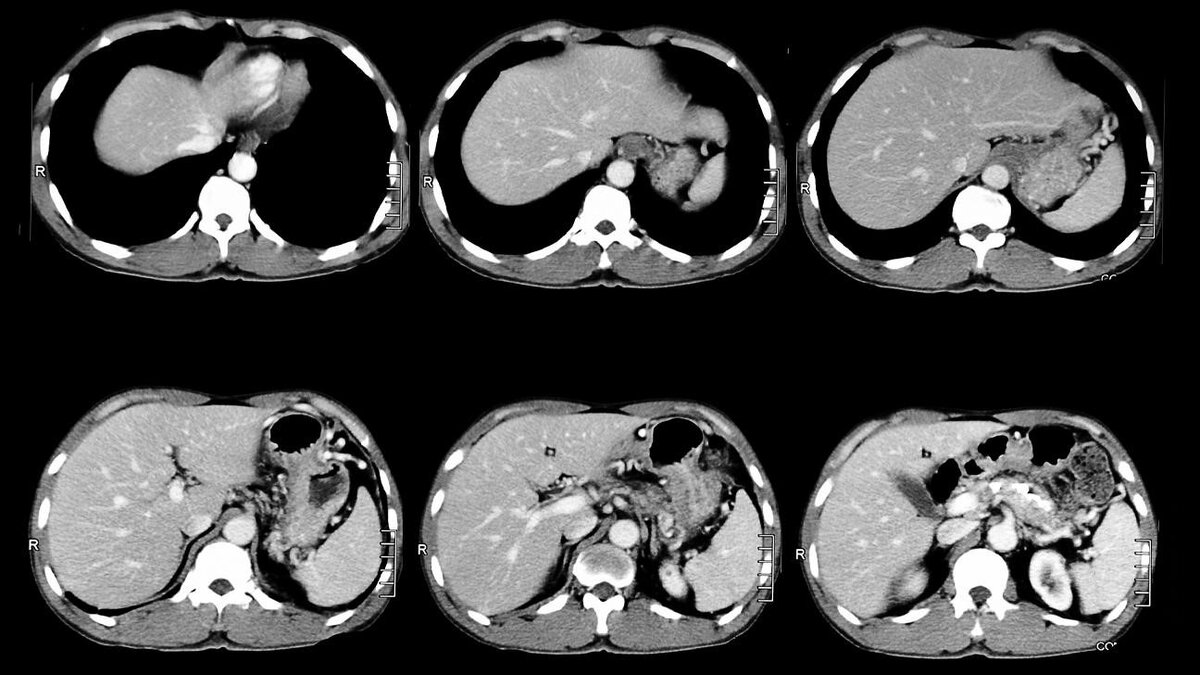

Компьютерная томография (КТ) — это один из способов аппаратной диагностики, который совмещает возможности рентгенографии и компьютерных технологий. Прибор измеряет скорость рентгеновских лучей, “прошивающих” тело пациента. В результате врач получает горизонтальные или осевые срезы объекта исследования в виде детальных объемных изображений.

КТ брюшной полости, в том числе контрастное, необходимо, чтобы исследовать эту область и забрюшинное пространство. Таким образом можно уточнить информацию о заболеваниях желчного пузыря, печени, почек, поджелудочной железы, желудка, селезенки, двенадцатиперстной кишки и других внутренних органов.

Компьютерная томография визуализирует анатомические особенности и структуру органов брюшной полости и в забрюшинном пространстве. Это желудок, селезенка, печень, кишечник, желчный пузырь, поджелудочная железа и почки с надпочечниками и мочеточниками.

На снимках различаются кровеносные сосуды и нервы, состояние костной ткани соответствующих отделов позвоночника.

Главное преимущество КТ-метода в том, что он детально высвечивает изменения патологического характера на ранних стадиях или когда их не заметили на других исследованиях брюшного отдела. Особенно хорошо это видно на снимках контрастного исследования.